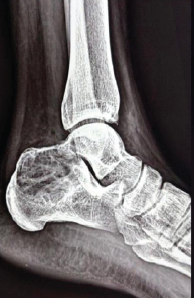

Calcaneal Giant Cell Tumor Masquerading as Lateral Ankle Sprain – A Rare Case Report and Review of Literature

Eshaan Mishra , Nirmal Chandra Mohapatra , Soumitesh Sibananda Das , Archana Mishra

………………………………p.219-223